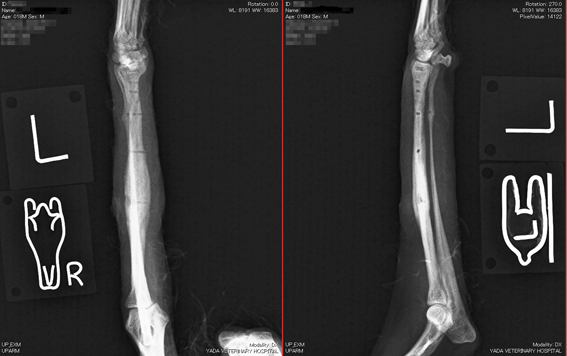

トイプードル。

体重3kg、6か月齢

左橈尺骨遠位の骨折。

写真上段: 手術前

写真中段: 手術直後

写真下段: 抜ピン後

手術後1ヶ月半で抜ピンしました。

骨に黒く写る線は、ピンの入っていた痕です。